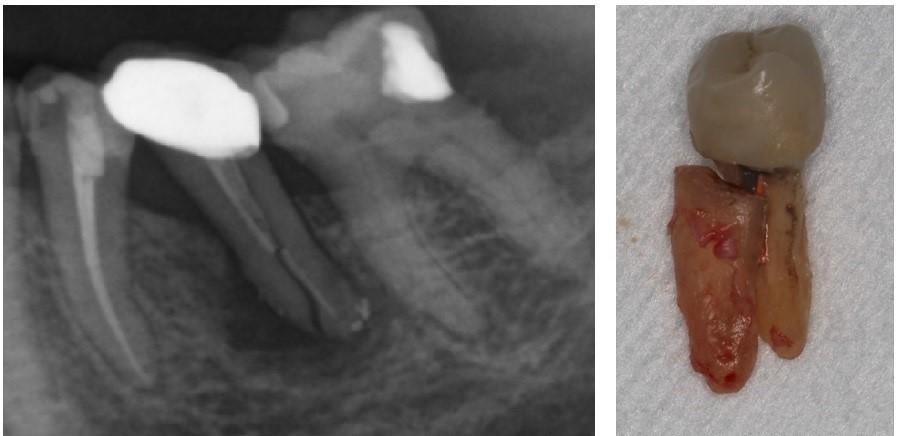

牙醫會以照X光片和臨床病徵,判斷裂牙的術後情況(Prognosis),與病人討論不同的治療方案。舉例當牙齒裂紋並沒有裂愈深,裂向牙房神經線,而剩餘的牙齒結構完整,牙醫會嘗試以補牙物料或牙套修復及保護牙齒。但如果裂紋已經深入牙房神經線,就有需要先進行根管治療,然後才可進行修復。再者,如果裂紋已裂到牙齒深處,例如裂到牙肉以下或者牙房底部,情況便不容樂觀,牙醫會與病人討論牙齒的去留,可能有需要拔牙。